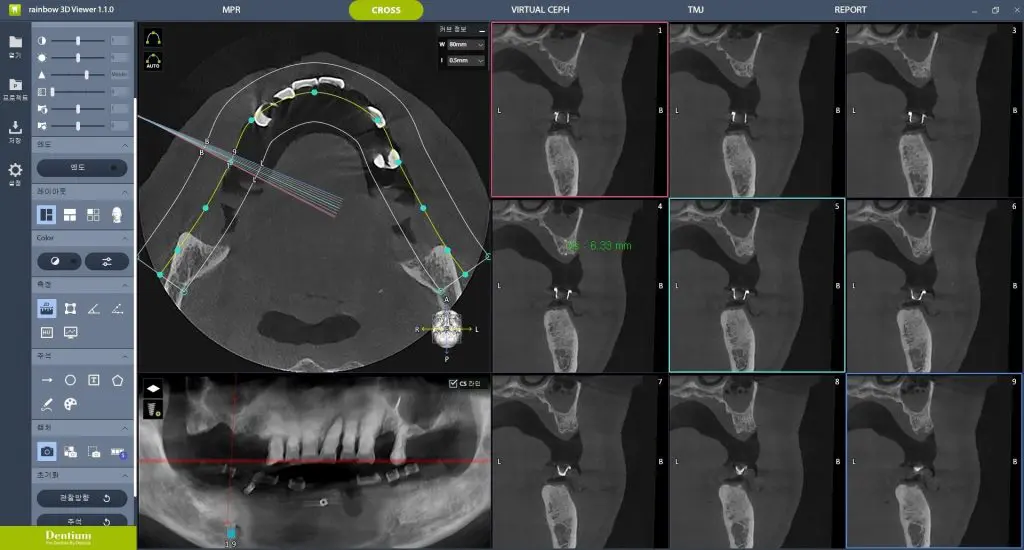

1. 정밀 진단 · 3D 분석

디지털 풀아치 임플란트는 한 턱에 4~6개의 임플란트로 전체 치아 기능을 회복하는 치료입니다. 먼저 3D CT, 파노라마, 디지털 구강 스캐너를 통해 잇몸뼈의 두께·밀도·신경 위치를 3차원으로 분석합니다. 이 단계에서 임플란트가 가능한 뼈 영역과 피해야 할 위험 구간을 명확히 구분합니다.

2. 디지털 수술 계획 · 가상 시뮬레이션

수집된 데이터를 기반으로 컴퓨터 상에서 가상 수술을 먼저 진행합니다. 임플란트의 개수, 위치, 각도, 깊이를 모두 수치로 계산하며, 뼈이식이 필요 없는 최적의 식립 지점을 우선적으로 설계합니다. 이 과정 덕분에 수술은 감각이 아닌 계획 기반으로 진행됩니다.